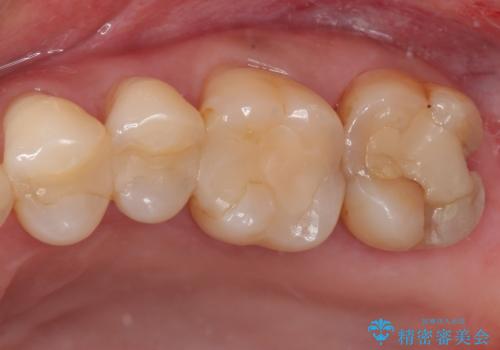

根尖病変が原因で、膿が出てきている歯があったため、仮歯を置き換える際に根管治療を行うこととしました。

仮歯を変えたことで歯肉の腫れは引き、根管治療も功を奏して膿の出口はきれいに消退しました。